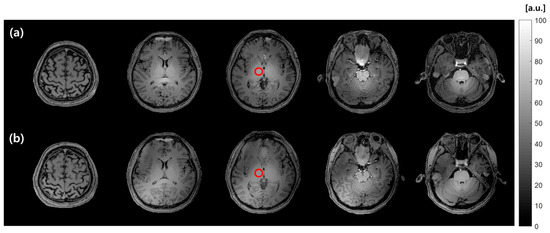

Figure 6 illustrates an FA map of the phantom acquired using 1H STBC RF coil, 23Na STBC RF coil, and 1H/23Na DMBC RF coil. For the 1H images, the FA map uniformity of 63.4% with 1H STBC RF coil and 59.8% with 1H/23Na DMBC RF coil were achieved. Similarly, for 23Na FA mapping, the uniformity was high at 87.8% for 23Na STBC RF coil, with 1H/23Na DMBC RF coil achieving a nearly equivalent uniformity of 84.4%.

Figure 6. 1H FA map (nominal FA: 60°) of phantom obtained using (a) 1H STBC RF coil and (b) 1H/23Na DMBC RF coil. 23Na FA map (nominal FA: 45°) obtained using (c) 23Na STBC RF coil and (d) 1H/23Na DMBC RF coil.

In the assessment of the RF coil performance for 1H MRI, SNR maps using 1H STBC and 1H/23Na DMBC RF coils are presented in Figure 7. The mean SNR value in ROI was 83.3 for 1H STBC RF coil and 77.9 for 1H/23Na DMBC RF coil, indicating a 6.5% SNR reduction with the DMBC RF coil.

Figure 7. SNR maps of in vivo human head 1H MR images acquired with (a) 1H STBC RF coil and (b) 1H/23Na DMBC RF coil. Red circles indicate the ROI for the SNR measurement.

Similarly, for the 23Na MRI test, the SNR maps of a human head are presented in Figure 8. The maps compare MR images acquired using 23Na STBC and 1H/23Na DMBC RF coil. The mean SNR values within the cerebrospinal fluid (CSF) ROI were 41.9 vs. 39.8 for STBC 23Na and 1H/23Na DMBC RF coil, respectively. This minor difference represents a nominal 5.4% reduction in SNR with the 1H/23Na DMBC RF coil, which is nearly comparable to the performance of the 23Na STBC RF coil.

Figure 8. SNR maps of 23Na MR images of an in vivo human head using (a) 23Na STBC RF coil and (b) 1H/23Na DMBC RF coil. Red circles overlaid on CSF designate the area for SNR measurement.